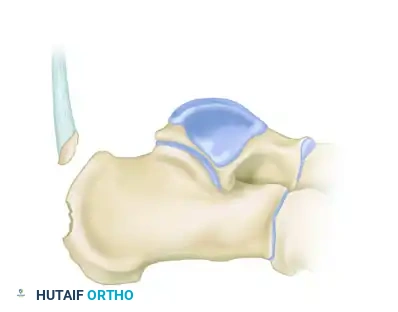

Understanding the morphology of the avulsion is critical for selecting the appropriate fixation strategy. These fractures are generally classified into three distinct types:

Type I: Sleeve Fracture

A thin sliver of cortical bone is avulsed from the posterior tuberosity, often involving the direct insertion of the Achilles tendon.

Type II: Beak Fracture

An oblique fracture exiting dorsally, creating a distinct "beak" fragment. This fragment is highly prone to proximal displacement due to the Achilles tendon.

Type III: Infrabursal Fracture

An avulsion fracture occurring lower on the tuberosity, typically sparing the primary Achilles insertion but involving the retrocalcaneal bursa region.

Below is an example of a severe calcaneal avulsion with a large fragment threatening the posterior envelope: